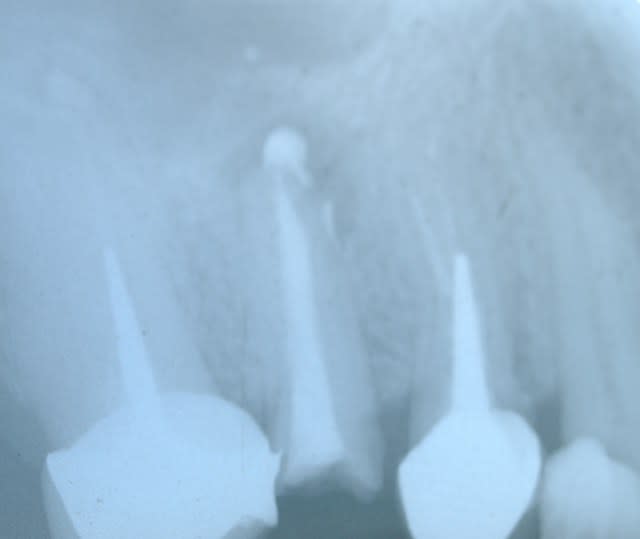

La couronne semble bien, le tenon aussi.

Le traitement endo bien que pas très radio opaque semble bon.le traitement endo a été fait il y a un moment d après ce que tu dis.

Peut être une fracture?, une fissure ou un abcès endo- paro?

a mon avis la dentiste a foré la racine pour preparer l inlay core et a du decoller le cone de gutta.

lors du scellement de l inlay core ,le ciment a du fuser a l apex et necroser l os sous jacent

dans ce cas la reprise d endo ne sert a rien .

Sauf de chasser le reste de ciment dans le canal.

Pour etre sur il faut tout pousser au fond du peri apex et d y aller voir.

BINGO la bestiole apparait a l apex . tu vois le petit machin blanc qui est sorti ?

Et pour la "bestiole" que tu vois apparaître à l'apex, ce peut être de la Gutta, du ciment d'obturation...